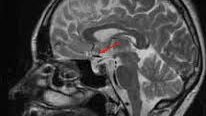

Из разговора с пациенткой перед обследованием : - Мария Петровна, вы не первый раз делаете МРТ головного мозга? - Нет, уже четвертый за последние 3 года! - А зачем, с какой целью? - Ну как зачем!? У меня обнаружили кисту, и теперь я её наблюдаю! Смотрим протокол предыдущего исследования. Действительно, ранее в другом центре у нее была найдена т.н. пинеальная киста (она же "киста шишковидной железы"). Однако, по современным представлениям она не требует многократного повторения МРТ с оценкой динамики, но пациентке об этом не сказали...